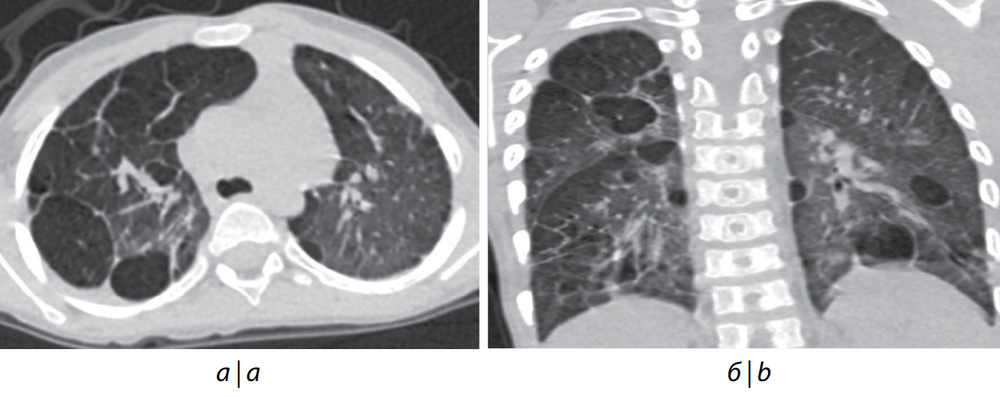

Все пациенты были женского пола; 5 из 6 детей наблюдались в клиниках с рождения из-за ранней манифестации ДН, длительной потребности в респираторной терапии, кислородотерапии. У всех пациентов по данным МРТ головного мозга была выявлена ПНГ. Диагноз эпилепсии был установлен только 2 детям. У всех наблюдавшихся детей была задержка психомоторного развития различной степени. 4 из 6 детей страдали ВПС, у такого же количества по данным ЭхоКГ была установлена дисплазия клапанов сердца, у 5 детей была диагностирована ЛГ, во всех случаях потребовавшая, кроме кислородотерапии, назначения препаратов ЛАГ-специфической терапии. «Золотым» стандартом оценки давления и сопротивления в сосудах малого круга кровообращения, а также посткапиллярной ЛГ является ангиокардиография [15]. В 4 из 6 случаев это исследование было выполнено после назначения ЛАГ-специфической терапии, т. к. в связи с возрастом, массой тела и тяжестью состояния детей не представлялось возможным выполнить её ранее. В 1 случае исследование не было выполнено из-за тяжести состояния ребёнка, в другом оно не было рекомендовано из-за отсутствия ДН, недостаточности кровообращения и изменений при ЭхоКГ. Дилатация восходящей аорты — грозное проявление патологии, ассоциированной с мутацией в гене FLNA, в основном встречающееся после 5 лет жизни и часто связанное с наличием двустворчатого аортального клапана [10]. В нашей серии наблюдений по данным проведённых ЭхоКГ и компьютерной томографии органов грудной клетки только в 1 случае была выявлена дилатация восходящей аорты, которая могла быть усугублена наличием исходно двустворчатого аортального клапана с умеренной степенью стеноза. Также в исследовании представлен пациент с нерестриктивным дефектом межжелудочковой перегородки, что делает невозможным продолжение ЛАГ-терапии (пациент № 6). Данному пациенту было проведено хирургическое закрытие дефекта межжелудочковой перегородки. У 5 детей по данным компьютерной томографии органов грудной клетки были выявлены очаги консолидации лёгочной паренхимы, эмфизематозные изменения, мозаичная пневматизация, линейные фиброзные тяжи (рис. 1). У пациента № 3 сопутствующей патологией явилась диафрагмальная грыжа, потребовавшая проведения оперативного вмешательства в неонатальном периоде. Пациенты с мутациями в гене FLNA часто испытывают трудности при кормлении. У пациента № 6 из-за сочетанной грубой задержки развития, выраженной дыхательной и неврологической патологии были выполнены гастростомия и трахеостомия. В 2 случаях наступил летальный исход: у пациента № 2 — от ДН, кризовой ЛГ на фоне поражения лёгких респираторно-синцитиальной вирусной этиологии (иммунизация паливизумабом не проводилась) в возрасте 1 года; у пациента № 5 — от сердечной недостаточности на фоне кризового течения ЛГ, усугубившегося в связи со стоматологическим оперативным вмешательством в возрасте 2 лет.

Рис. 1. Компьютерная томография органов грудной клетки пациента № 1 в возрасте 3 лет.

а — аксиальный срез; б — фронтальный срез. Эмфизематозные участки округлой формы с чёткими контурами уплотнения по периферии.

Fig. 1. CT scan of the chest of patient No. 1, 3 years.

а — аxial section; b — frontal section. Emphysematous rounded areas with clear contours of compaction along the periphery.